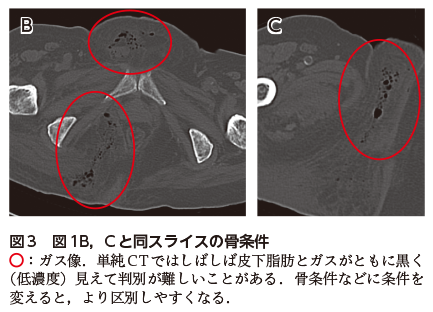

• A1:右側会陰部の皮下や筋内などにガス像が認められる(図1).その周囲には強い脂肪織濃度上昇がみられる(図1B).

臨床的には,組織壊死に伴う会陰部を中心とした赤黒い腫脹(図2)と悪臭が特徴的である.特に深部での病変の広がりを評価するためにCTが撮影されることが多く,皮下や筋内などのガス像の検出が診断に有効である.造影CTでは大小の膿瘍形成が確認されることも多いが,あくまでもガス像が特徴と考えるとよい.単純CTではしばしば皮下脂肪とガスがともに黒く(低濃度)見えて判別が難しいことがあるが,骨条件などに条件を変えると区別しやすくなる(図3).MRIは軟部組織の炎症の範囲,膿瘍形成の有無など評価するのに有用ではあるが,ガスの検出についてはCTに劣るだろう.

図1